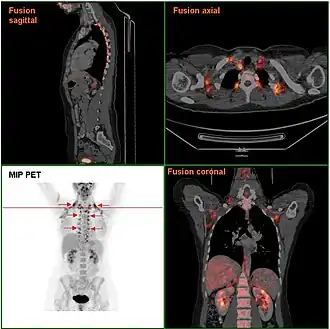

Brown adipose tissue in a woman shown in a FDG PET/CT exam | |

BAT's presence in adult humans was discovered in 2003 during FDG-PET scans to detect metastatic cancers.[12][13] Using these scans and data from human autopsies, several deposits have been identified. In infants, brown adipose tissue deposits include: interscapular, supraclavicular, suprarenal, pericardial, para-aortic and around the pancreas, kidney and trachea.[14] These deposits gradually get more white fat-like during adulthood. In adults, the deposits that are most often detected in FDG-PET scans are the supraclavicular, paravertebral, mediastinal, para-aortic and suprarenal ones.[15][7] It remains to be determined whether these deposits are 'classical' brown adipose tissue or beige/brite fat.[16][17]

Studies using positron emission tomography scanning of adult humans have shown that brown adipose tissue is still present in most adults in the upper chest and neck (especially paravertebrally). The remaining deposits become more visible (increasing tracer uptake, meaning more metabolically active) with cold exposure, and less visible if an adrenergic beta blocker is given before the scan. These discoveries could lead to new methods of weight loss, since brown fat takes calories from normal fat and burns it. Scientists have been able to stimulate brown fat growth in mice.[26][27][28][29] One study of APOE knock out mice showed cold exposure could promote atherosclerotic plaque growth and instability.[30] The study mice were subjected to sustained low temperatures of 4 °C for 8 weeks which may have caused a stress condition, due to rapid forced change rather than a safe acclimatisation, that can be used to understand the effect on adult humans of modest reductions of ambient temperature of just 5 to 10 °C. Furthermore, several newer studies have documented the substantial benefits of cold exposure in multiple species including humans, for example researchers concluded that "activation of brown adipose tissue is a powerful therapeutic avenue to ameliorate hyperlipidaemia and protect from atherosclerosis"[31] and that brown fat activation reduces plasma triglyceride and cholesterol levels and attenuates diet-induced atherosclerosis development.[32]